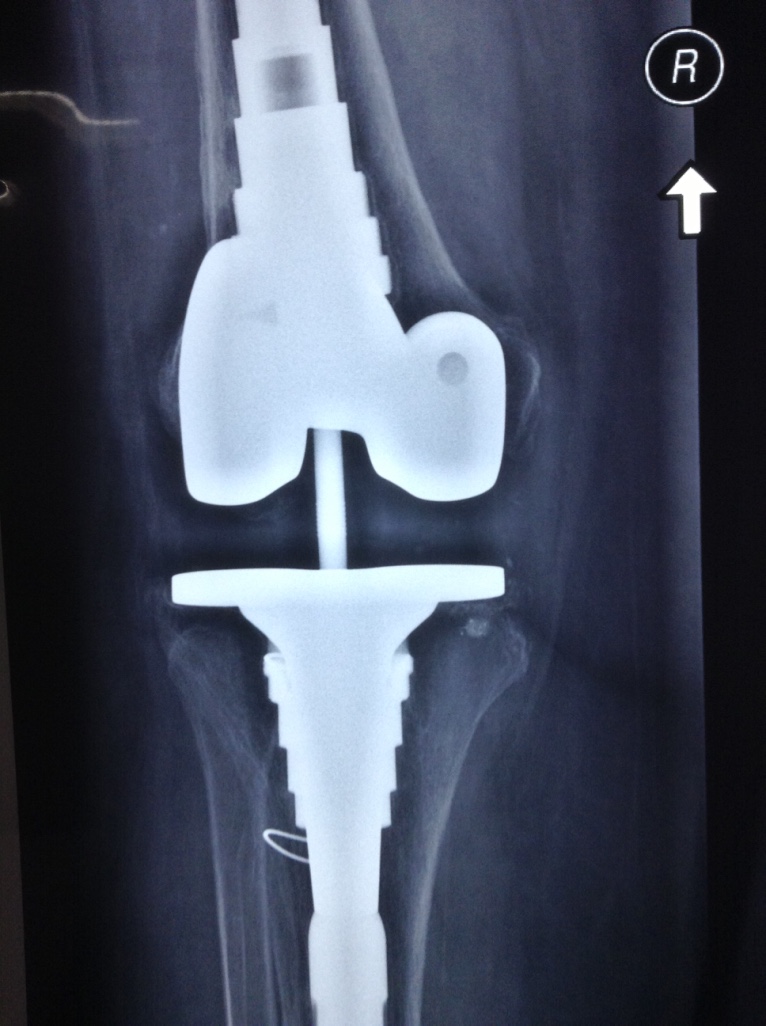

Revision Total Knee Replacement After a fructure

• Revision Total Knee Replacement After a fructure